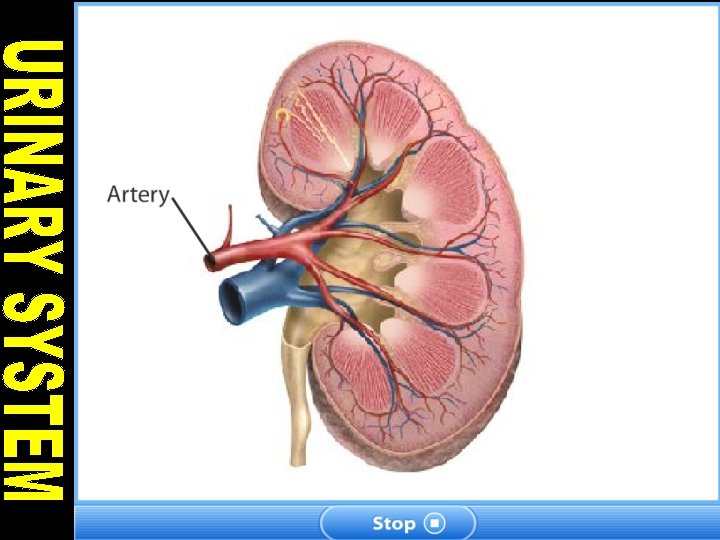

KIDNEY • Kidneys are bean shaped organs that filtere 180 lt. blood in a day. • Blood is come into kidney by renal artery. • Filtered blood leaves from kidney by renal vein.

STRUCTURE OF KIDNEY 1. Cortex: It contains glomerulus and Bowman’s capsules. 2. Renal Capsule: It surrounds and protects the kidneys.

3. Medulla: It is located under the cortex and has malphigian pyramids. Malphigian pyramids contains urine collecting canal and loop of henle. 4. Pelvis: It is innermost part of kidney. The urine is collected in pelvis.